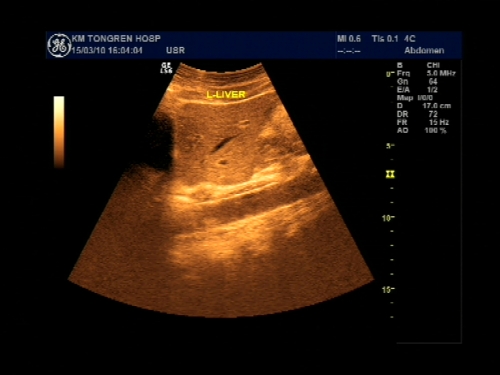

超声声像图能显示肝脏切面形态、大小、肝内实质结构、管道系统及肝周邻,并能根据肝内管道系统区分肝脏各叶、各段,对病变进行定位诊断。彩色多普勒超声能显示肝脏的血流,并能对肝脏的血流动力学参数进行测定,不仅能诊断肝脏的血管病变,还能了解正常肝脏及病变肝脏的血供及回流状态,目前已成为临床诊断肝脏疾病的常规检查方法。

肝脏超声分区

肝脏超声以肝内管道的一级、二级、三级分支未基础,将肝脏分为五叶8段:尾叶(Ⅰ)、左外叶上段(Ⅱ)、左外叶下段(Ⅲ)、左内叶(Ⅳ)、右前叶下段(Ⅴ)、右后叶下段(Ⅵ)、右后叶上段(Ⅶ)、右前叶上段(Ⅷ)